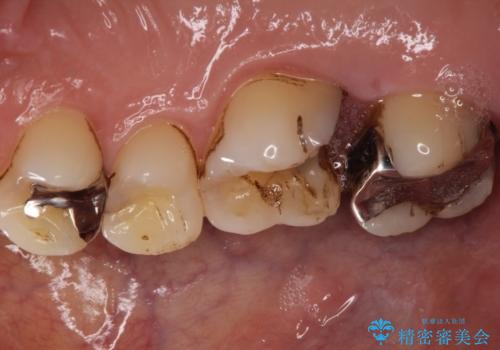

- 銀歯が外れて、中が虫歯になっているところがありました。

虫歯を取り除き、ゴールドインレーを装着する治療計画としました。